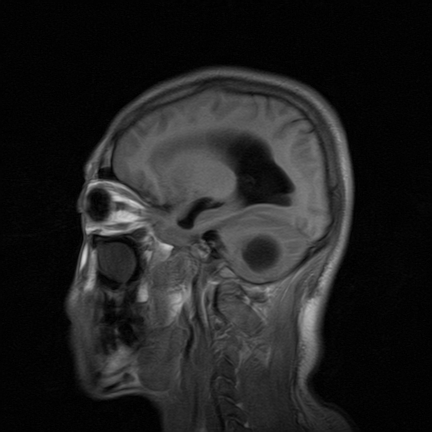

标题: MRI2064:少见病例。男性52,视力下降多年。 [打印本页]

标题: MRI2064:少见病例。男性52,视力下降多年。

考虑第四脑室室管膜瘤并梗阻性脑积水;部分性空蝶鞍;左侧上颌窦粘膜下囊肿。

加左上颌窦囊肿

2、左侧上颌窦及蝶窦囊肿。

小脑蚓部胶质脑膜瘤突入四脑室;肿瘤内见血管流空信号和钙化信号.

比较典型的脉络丛乳头状瘤并脑积水,鉴别小脑蚓部血管母细胞瘤。